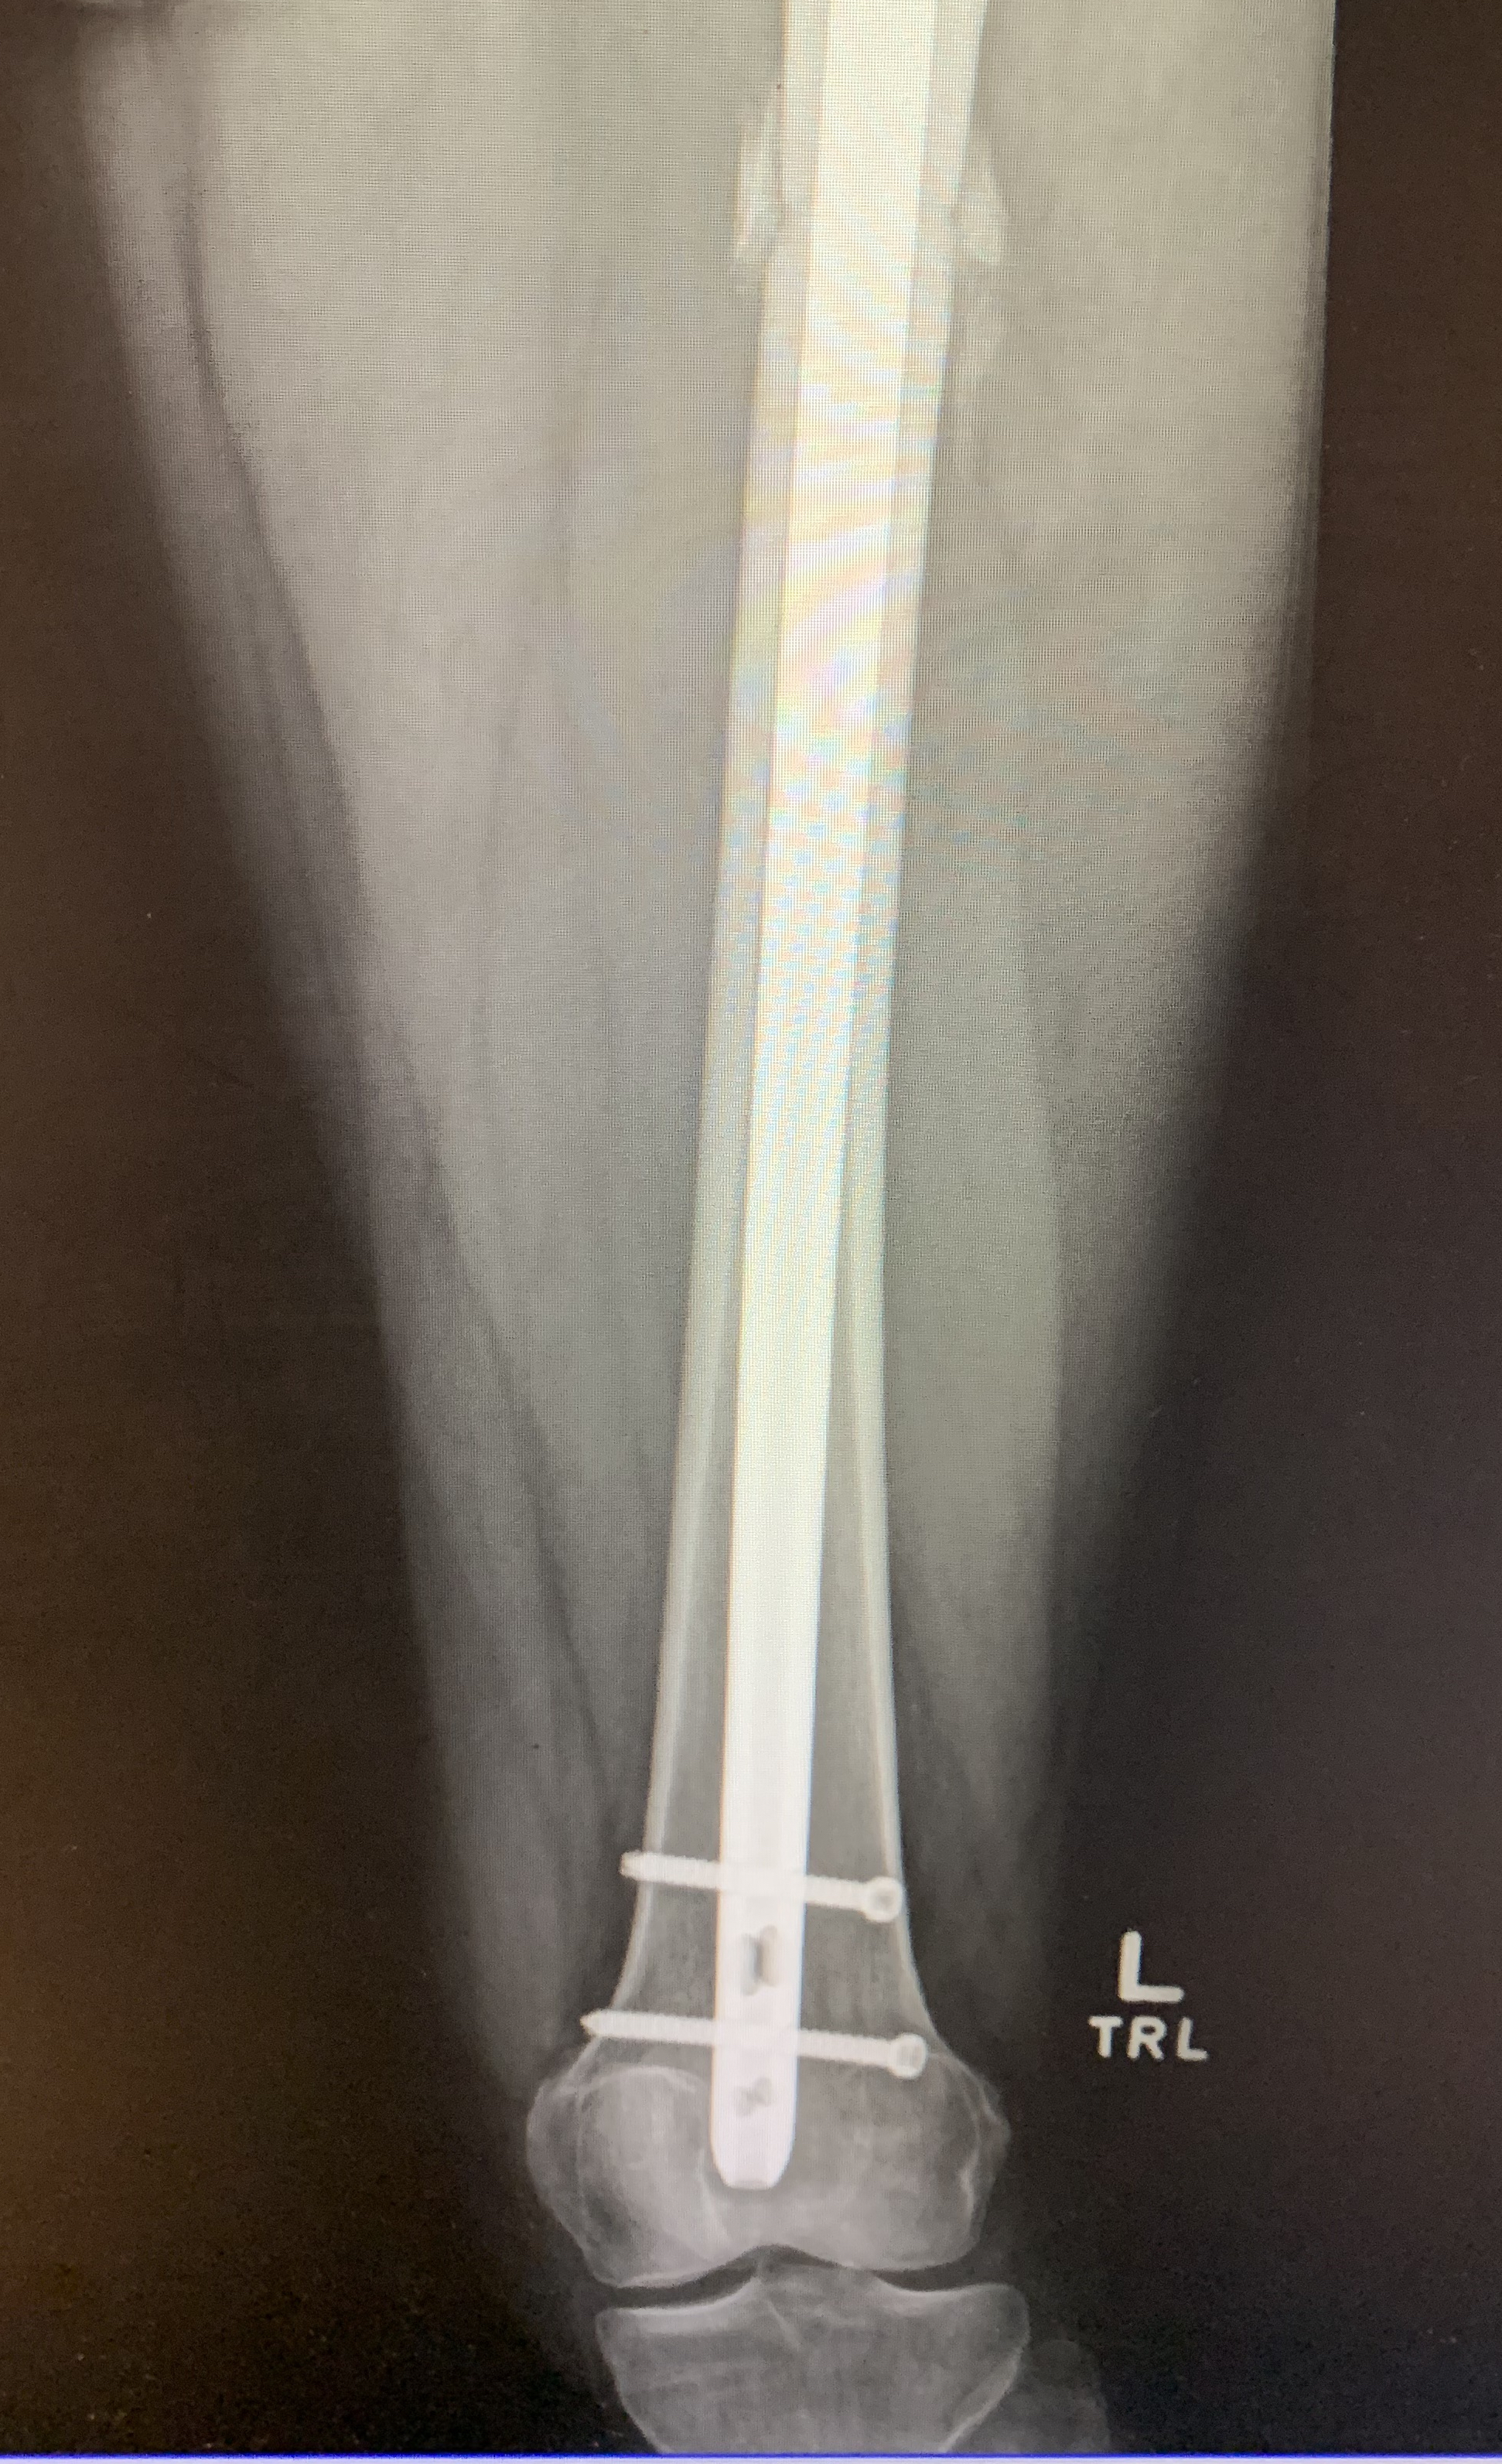

Check out below images of my hip! Can you see the rod and screws? Can you see where the intentional osteotomy (fracture) occurred? Can you see the bone fragments that “spewed” out the top of my femur? Crazy to think this is my leg now!

My left foot is pretty sore because I am walking on it differently now. I no longer walk flat footed and the outside arch and calf are yelling at me. My left knee is not giving me much trouble yet, but my surgeon reports that in the future I may need the remove these screws to avoid discomfort. We will see. Also, he noted some extra bone fragments created during the surgery at the insertion site of the rod into the femoral head. He says that he may have to go in and remove those in the future as well. Either way, he is very happy with how things look.